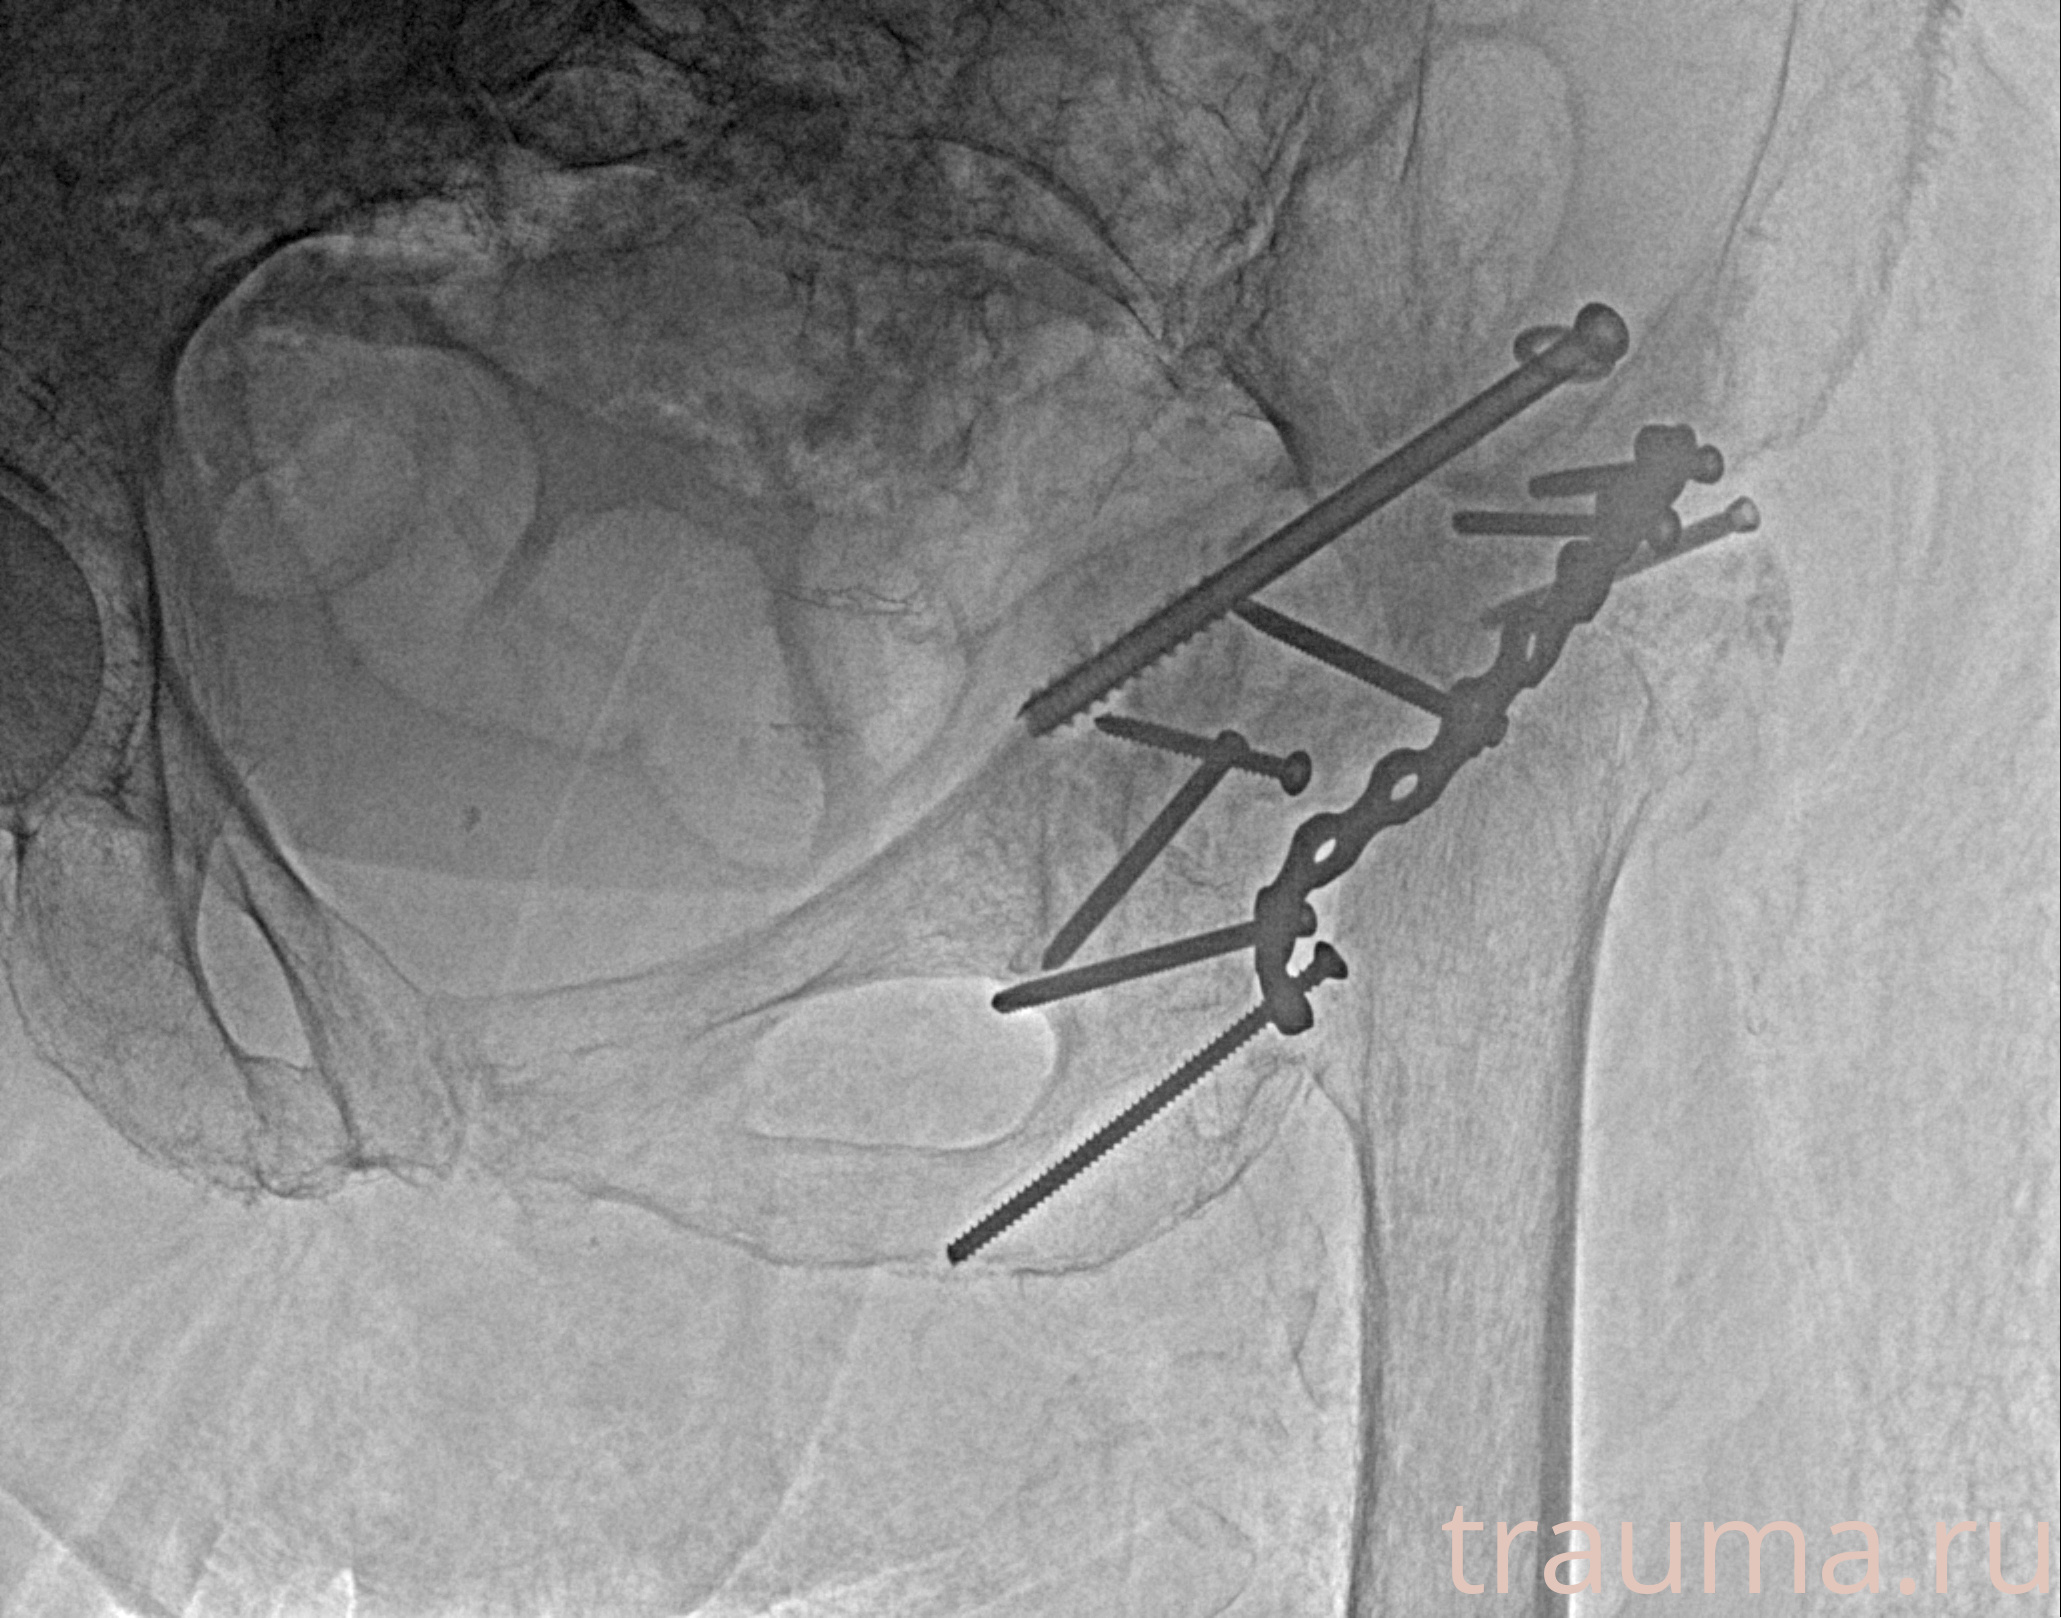

Рентгенограммы

Рентген на дому: по вашему адресу приезжает врач-рентгенолог, травматолог-ортопед с мобильным рентгеновским аппаратом, проводит диагностику травмы или заболевания, делает необходимые рентгенограммы, дает рекомендации по дальнейшему лечению. Получить качественные снимки в домашних условиях возможно благодаря уникальной методике, разработанной МосРентген Центром для института  Склифосовского